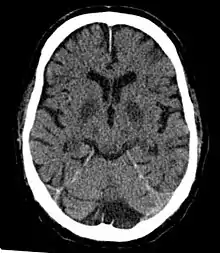

Diagnosis

Classification

Cerebral hypoxia is typically grouped into four categories depending on the severity and location of the brain's oxygen deprivation:[20]

- Focal cerebral ischemia – A stroke occurring in a localized area that can either be acute or transient. This may be due to a variety of medical conditions such as an aneurysm that causes a hemorrhagic stroke, or an occlusion occurring in the affected blood vessels due to a thrombus (thrombotic stroke) or embolus (embolic stroke).[21] Focal cerebral ischemia constitutes a large majority of the clinical cases in stroke pathology with the infarct usually occurring in the middle cerebral artery (MCA).[22]

- Cerebral infarction – A "stroke", caused by complete oxygen deprivation due to an interference in cerebral blood flow which affects multiple areas of the brain.